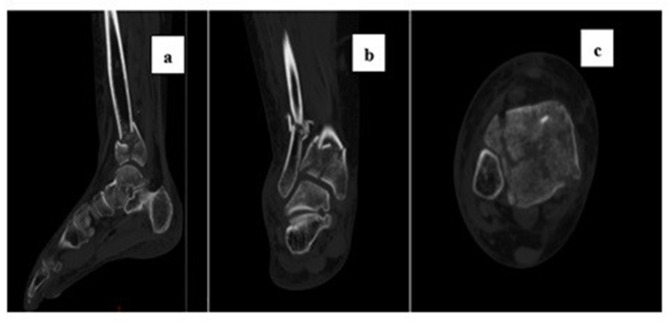

Patients and methods: In this single-center retrospective study, we collected adult (≥18 years old) patients with pilon fractures who underwent open reduction and internal fixation at Xi'an Honghui Hospital from January 2020 to July 2024 and had the cognitive ability to complete the questionnaire. Exclusion criteria included incomplete medical records, concurrent other foot fractures, or severe mental disorders. The preoperative central sensitization (CS) determination criteria were a score of ≥18 on the Chinese version of the 9-item Central Sensitization Inventory (CSI-9). The assessment indicators at baseline and the last follow-up included the Visual Analogue Scale (VAS) for pain, the American Orthopaedic Foot & Ankle Society Hindfoot Score (AOFAS), and the Hospital Anxiety and Depression Scale (HADS). Patients were divided into the CS group and the non-CS group based on whether they had a preoperative central sensitization state, and the differences in baseline characteristics, pain severity, functional performance, and psychological state between the two groups were compared.